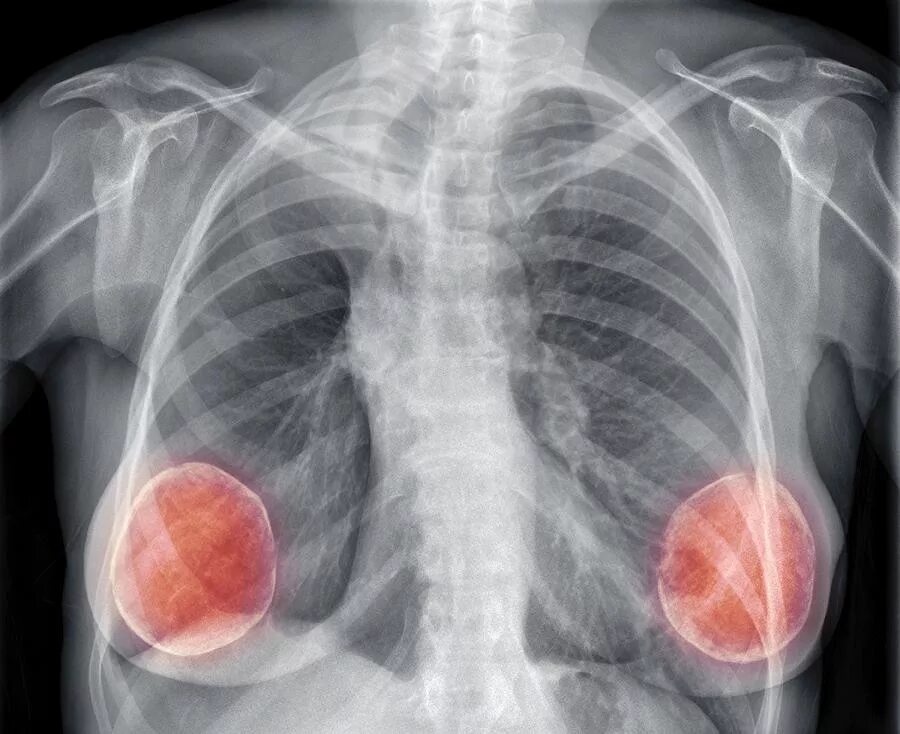

- Видимость имплантов на снимке: Сами грудные импланты будут видны на флюорографическом снимке в виде однородных округлых теней. Это совершенно нормально и не является признаком патологии. Опытный рентгенолог без труда отличит имплант от патологического образования.

Краткий и обнадеживающий ответ: наличие грудных имплантов не является противопоказанием к проведению флюорографии и не мешает обследованию легких. Современные грудные импланты, как правило, изготовлены из силикона или солевого раствора. Эти материалы хорошо пропускают рентгеновские лучи, что позволяет получить достаточно четкое изображение легких и других структур грудной клетки.